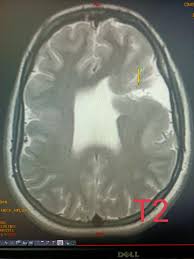

• Encéphalomalacie kystique: Ce type laisse des espaces remplis de liquide dans le cerveau là où le tissu est mort

• Porencéphalie: présence de kystes ou de cavités dans un hémisphère cérébral, souvent d'origine congénitale

DD: - kyste arachnoïdien

- schizencéphalie (fentes ou de fissures s'étendant du ventricule latéral au cortex, bordées par SG dysplasique)

- kyste épendymaire

- encéphalomalacie

- hydranencéphalie